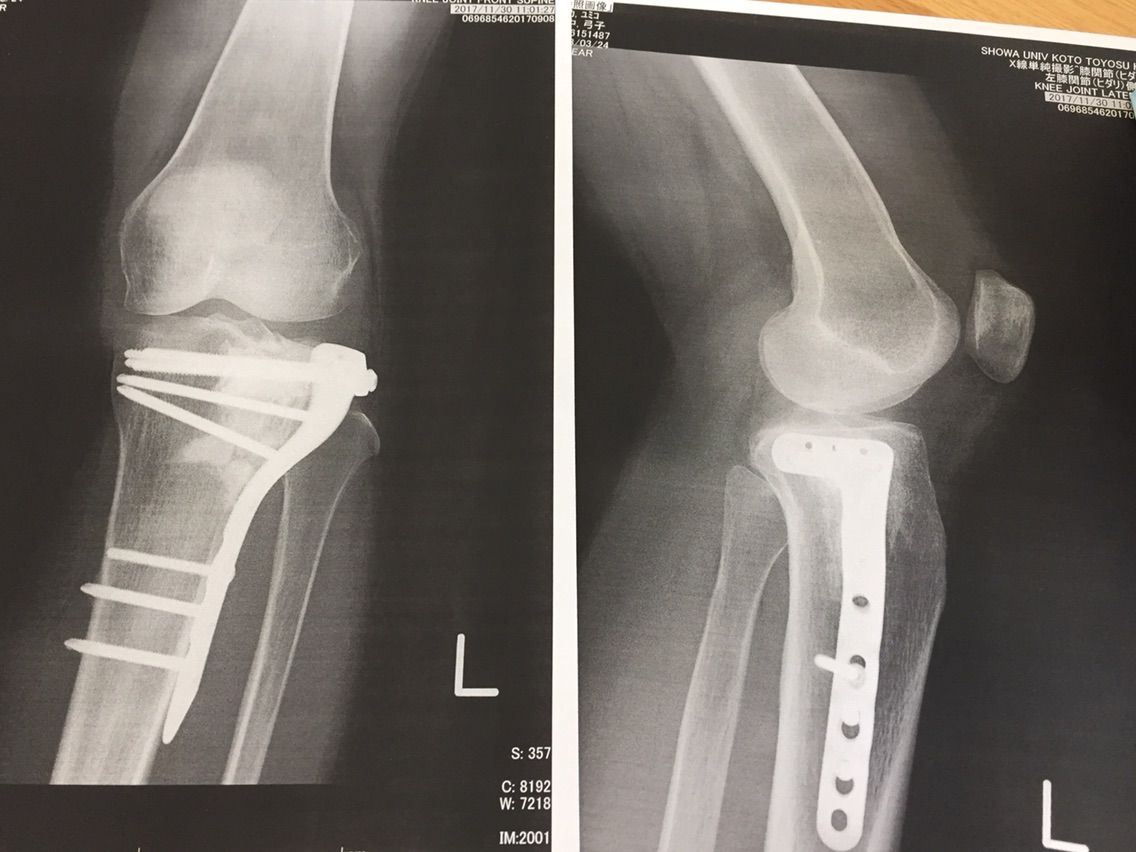

「確かにレントゲンをよく見ると、ほらこの下の方は、まだ角砂糖状態の人工骨が残ってて、隙間が埋まってきてないんですよね…」